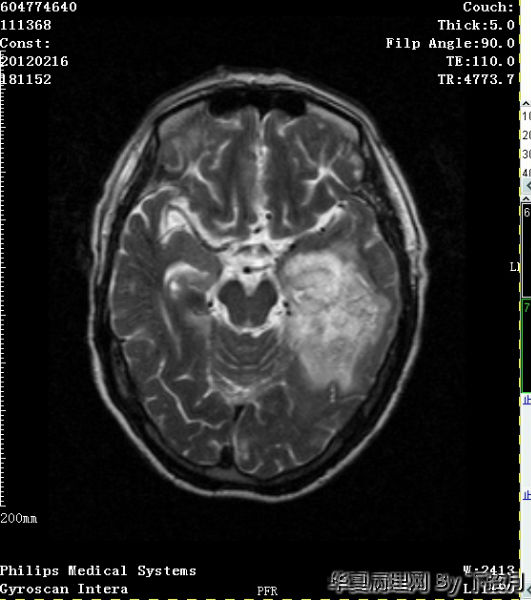

左侧颞叶及胼胝体膝部占位

左侧颞叶及胼胝体膝部占位图1

左侧颞叶及胼胝体膝部占位图3

左侧颞叶及胼胝体膝部占位图4

左侧颞叶及胼胝体膝部占位图18

左侧颞叶及胼胝体膝部占位图19

左侧颞叶及胼胝体膝部占位图20

粘液型乳头状室管膜瘤:好发于年轻人,几乎毫无例外位于圆锥-马尾终丝区。组织学Ⅰ肿瘤细胞围绕血管粘液样间质为轴心,排列成乳头状为特点。本例是老年人,位于左侧颞叶及胼胝体膝部,年龄和位置不太相符。另外本例Ki-67指数有点高。有点疑惑

从图1可见肿瘤似位于脑皮质外围,有粘液背景,部分如脊索瘤样,倾向于脊索瘤样脑膜瘤。